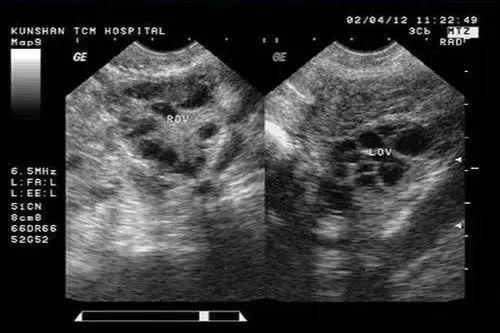

B超可以说是妇科检查的必查项目了,通过这种超声波检查,可以观察到你是否有宫颈疾病、子宫内膜疾病、子宫肌瘤等异常情况。

一些常见的妇科问题(如盆腔积液、多囊卵巢等),也都是可以通过B超观察到的。

B超检查的方式有3种:腹部B超、经阴道B超以及经直肠B超。

其中,腹部B超是最简单方便,也是更适合没有过*生活性**以及阴道部位存在异常的人的检查方式,但检查之前需要憋尿,相对来说也没有特别准确。

经阴道B超以及经直肠B超,不用憋尿,检查结果也更准确,但同样需要你放下“羞耻心”。(还是想再多啰嗦一句,都来医院检查了,“羞耻心”这种东西,就先暂时放下吧~)